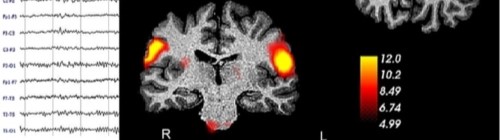

Focuses on the study of the central and peripheral nervous systems through neuroanatomy, molecular biology, neuropharmacology, electrophysiology, behavioral methods, computational modeling, and brain imaging. Research involves both human and animal models, including iPSCs and brain organoids, fostering interdisciplinary integration across biological, behavioral, and computational levels. - Clinical Neuroscience

Explores neurological and psychiatric disorders across the lifespan, with emphasis on genetic, epigenetic, and environmental risk factors. Techniques include electrophysiology, omics, eye-tracking, and brain imaging. Therapeutic interventions—such as non-invasive brain stimulation and psychosocial rehabilitation—are also studied as predictors of treatment response and efficacy. - Cognitive Neuroscience and Psychology

Research topics often span multiple areas, applying integrated methodologies to address questions related to brain function in health and disease (e.g., Alzheimer’s, Parkinson’s, epilepsy, chronic pain, autism).